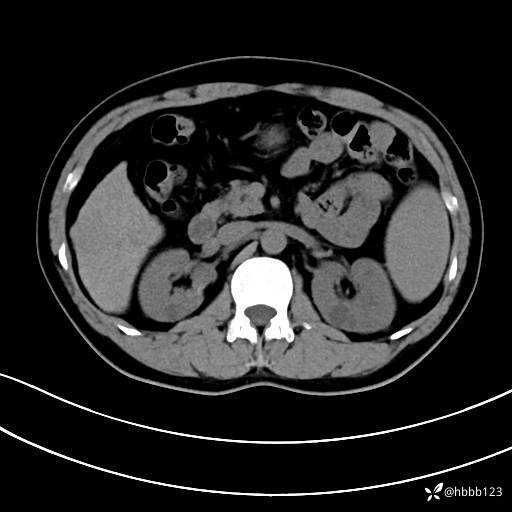

平扫: